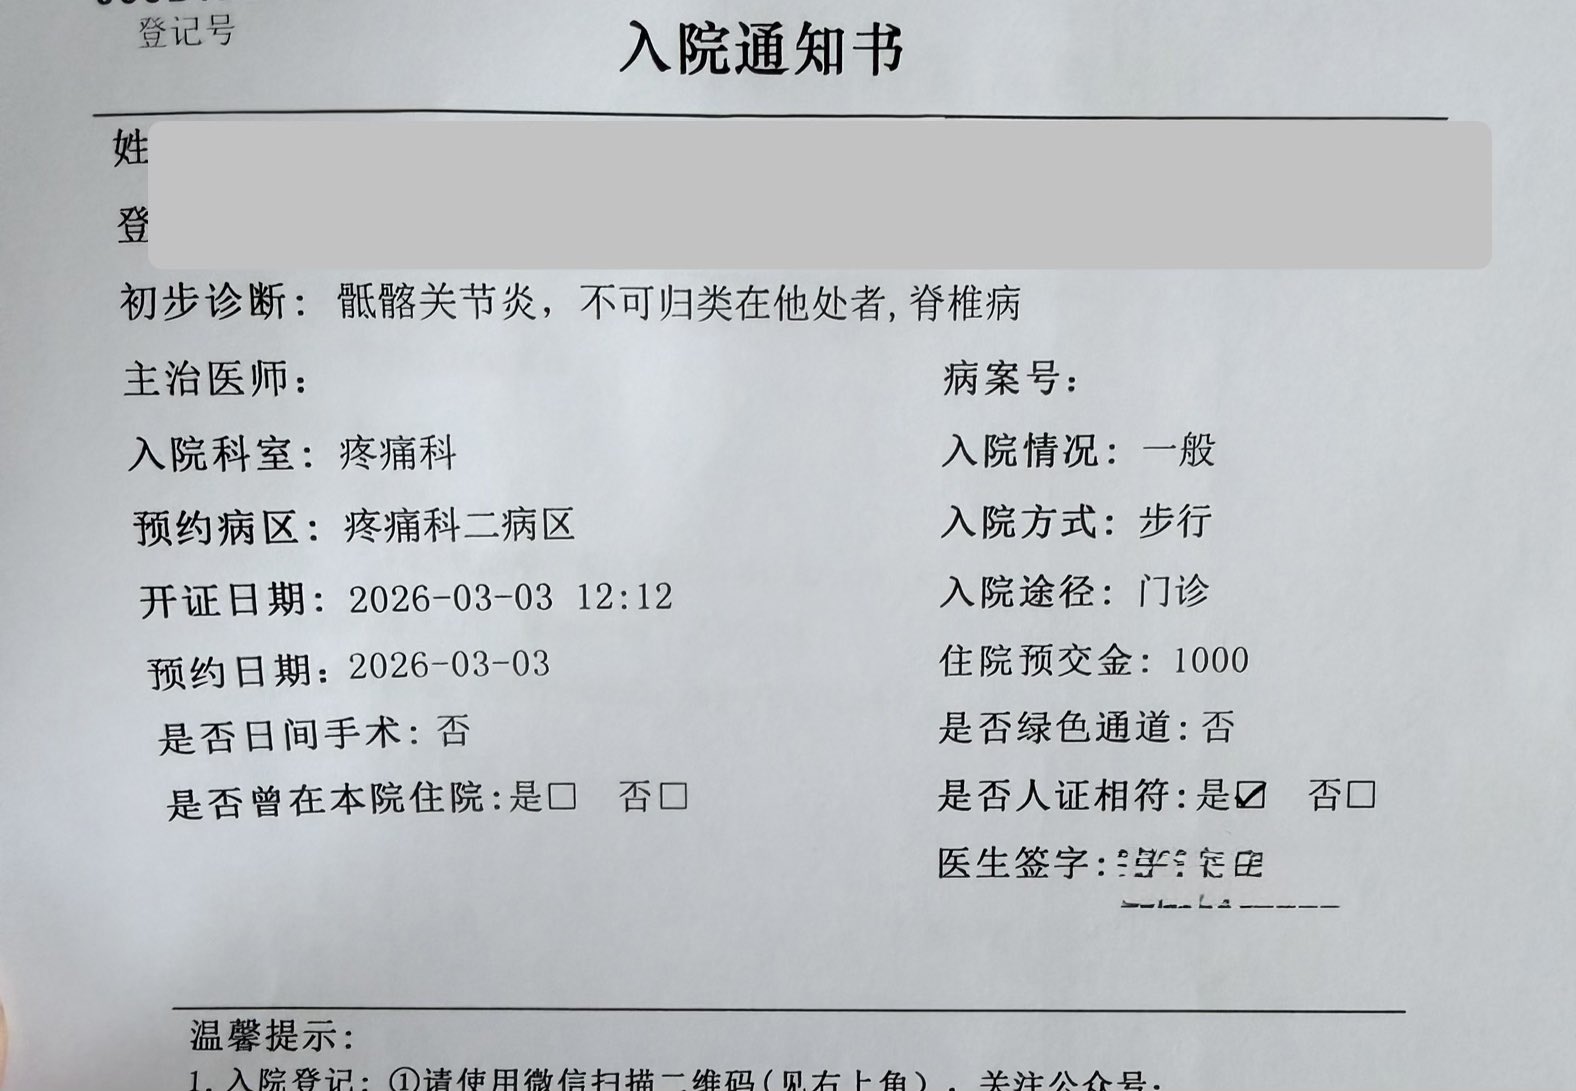

2026-03-03 14:25:15 UTC

地狱难度…救救我TT

目前好像还没有找到能治好的办法,脊椎的疼痛和内异症的都是。有一个关键字为血小板的治疗3k一针…不知道要做多少次,而且似乎也不确定效果

开了住院的单子但是还没决定要不要去。好想放弃啊…明明这样更轻松,坚持下去的理由到底是什么根本想不出来,为什么大家都说活着是正确的 https://t.co/aBYikEDvqG

炽烈已极 @AnIncandescence@Eternal1uv9 明确是先天性发育异常,Bertolotti综合征

炽烈已极 @AnIncandescence@Eternal1uv9 假关节把额外负荷传到骶髂关节可能形成了炎症,这是继发影响。后天生活(应该和我的专业有关)导致了加重